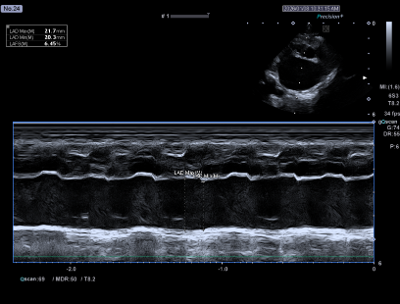

좌심방의 수축력(LA FS)은 6.5%로, 정상 기준(25% 이하)에 비해 현저히 저하된 상태였습니다. 이는 좌심방이 혈액을 밀어내는 기능이 크게 떨어졌다는 의미입니다.

환자의 심장초음파 사진(좌심방 수축력 6.5% 심한 감소 (정상 25%이내)) / 출처: 24시 동탄리더스동물의료원